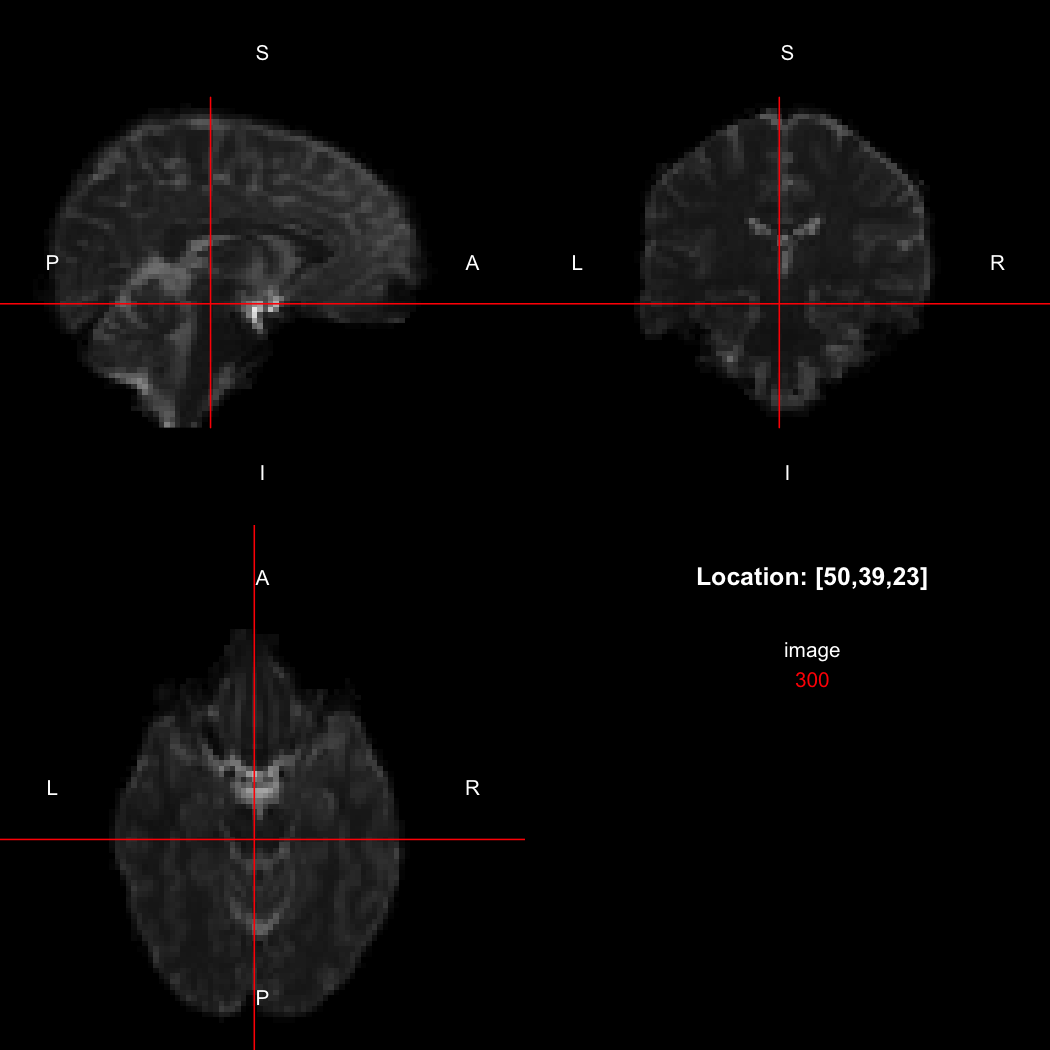

The package contains a basic image viewer, which can be used interactively or noninteractively to examine 2D or 3D images.

view(image)

By default, the viewer shows labels indicating image orientation, crosshairs pinpointing

the currently selected location, the numerical indices of the current

location, and the value of the image at that location. Options allow

each of these to be turned off, for the content of the bottom-right

panel to be customised entirely, for the colour scale to be changed, and

for additional images to be layered on top of the base image. See

?view for details.

## [1] "LAS"So, here, “LAS” means that the positive x-axis points left, the positive y-axis anterior and the positive z-axis superior. This is the so-called “radiological” orientation convention, and can be requested when viewing images for those who are used to it:

view(image, radiological=TRUE)

Notice the left (L) and right (R) labels, relative to the view shown

above. Setting the radiologicalView option to

TRUE will make this the default for all future views.

image[50,39,23]

## [1] 300